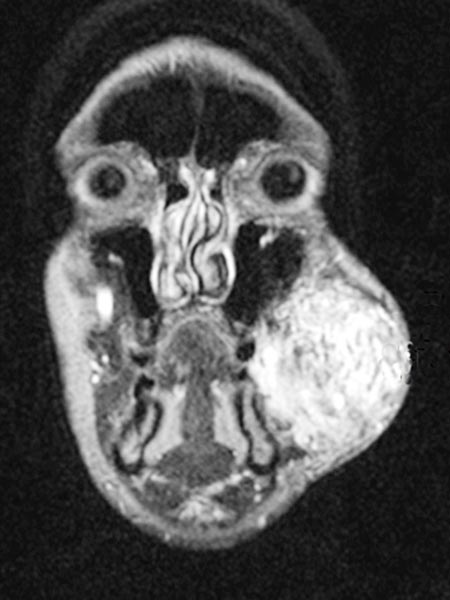

Die koronare, fettunterdrückte T1-gewichtete MRT nach Kontrastmittelgabe zeigt das inhomogene deutliche Enhancement der AVM, das typisch ist für eine AVM im Stadium der Proliferation (entsprechend der schnellen klinischen Vergrößerung) und gut mit dem Ödem in den T2-gewichteten Aufnahmen korreliert.

Koronare, T2-gewichtete, fettgesättigte MRT mit Ödem innerhalb der AVM sowie gut sichtbaren flow-voids durch die enthaltenen Arterien mit hohem Durchfluss.